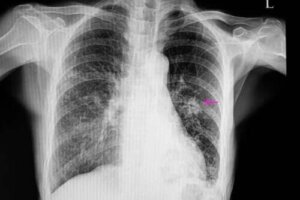

Cauzele acestei boli variază de la infecții la tumori. Cei mai mulți noduli pulmonari sunt descoperiți accidental atunci când se efectuează o scanare CT (tomografie computerizată) sau o radiografie.

În astfel de cazuri, nodulii vor avea un aspect neregulat, cu margini slab definite; acest lucru este vizibil la radiografie. De asemenea, nodulii cancerigeni sunt, de obicei, mai mici decât cei benigni. Factorii de risc care duc la apariția tumorilor maligne sunt:

După aflarea acestor informații, medicul trebuie să efectueze anumite teste imagistice pentru a localiza nodulul. În plus, imaginile îi vor permite să observe anumite caracteristici, cum ar fi forma și dimensiunea nodulului. Aceste valori sunt importante pentru diferențierea unui nodul benign de unul posibil malign.

Cel mai frecvent mod de a diagnostica nodulul pulmonar este prin radiografie toracică și tomografii computerizate. Pentru a afla cauza exactă a unui nodul pulmonar, medicii fac uneori biopsii, deoarece acestea le permit să analizeze țesutul.